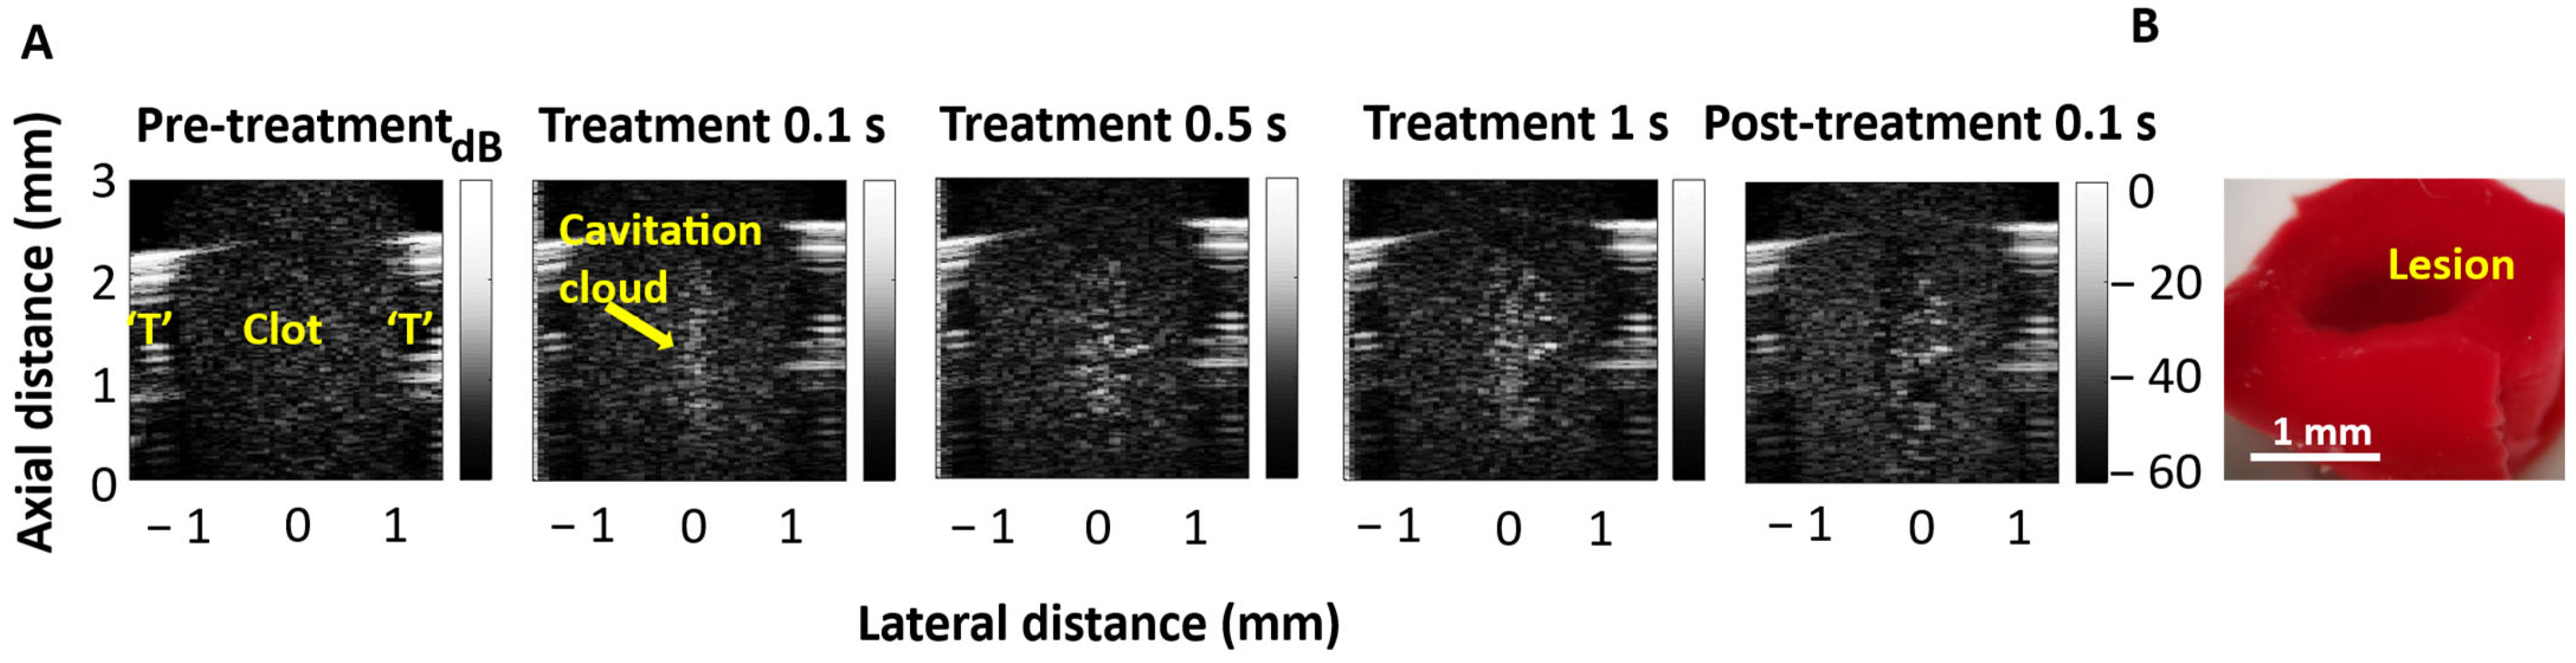

3.2. Cavitation Imaging and Cavitation Probability with Water-Filled Lumen

3.3. Self-Sensing Signals in Water-Filled Lumens

3.4. Self-Sensing Signals During Clot Treatments

4. Discussion